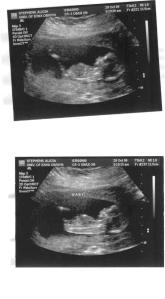

oK…..So, we are definitely not having twins! I will admit that I breathed a sigh of relief when I heard that….but we are definitely having one beautiful little baby! I am a little farther along then what the midwife predicted the first time…..just by about a week. SO, I am exactly where I predicted I was before my first appointment, at 13 weeks and 4 days!!!

Enjoy our 1st baby picture! I am telling you, I ran to a computer all day at work and stared at this picture all day. I could not stop thinking about the squirmy, tiny, little baby who did not want to stay still for the ultrasound! We are just so in love already and really feeling how REAL all of this is!